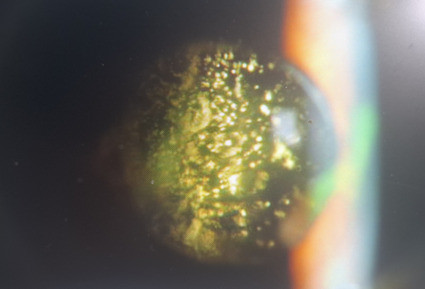

星狀玻璃體的病變,有很明顯的星狀沉積物漂浮在玻璃體中。(達特楊眼科提供)

此外,於晚上或關燈後,在燈下或以手電筒見到瞳孔的中央有上百成千星狀或雪花狀混濁點漂浮物,如聖誕節的飾物般閃爍,這就是星狀玻璃體的病變,此種混濁小點包含有鈣鹽或脂質的沉積物,漂浮於玻璃體中,患者本身無自覺症狀,也不影響視力,年齡越大者越常見,無特殊治療方法。一旦發現有星狀玻璃體,40%合併糖尿病,33%為高膽固醇,而44%的患者其三酸甘油脂值大於190 mg/dl,另外酗酒容易產生。